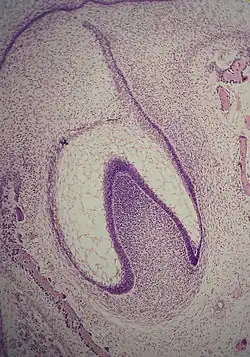

Histologic slide showing a tooth bud.

A: enamel organ

B: dental papilla

C: dental follicle

The tooth germ is an aggregation of cells that eventually forms a tooth.[2] These cells are derived from the ectoderm of the first pharyngeal arch and the ectomesenchyme of the neural crest.[1][3][4] The tooth germ is organized into three parts: the enamel organ, the dental papilla and the dental sac or follicle.